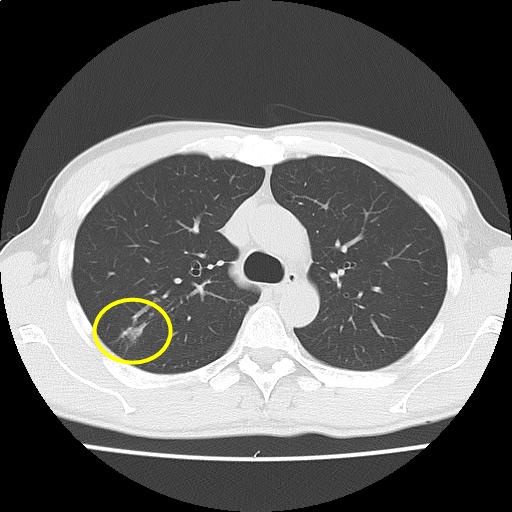

CTスライス1

(Findings)

右肺上葉の斑状影はやや濃度低下を示しており、炎症性変化を疑う。

中葉に気道に沿った粒状影および結節を認め、非結核性抗酸菌症などの慢性気道炎症が鑑別に挙がる。前回と比較してわずかに増悪。

両肺にブラを散見する。

縦隔リンパ節腫大および胸水を認めない。

(Impression)

右肺上葉斑状影:やや濃度低下しており、炎症性変化を疑う。

慢性気道炎症疑い:わずかに増悪。

単純CT上、背部痛の原因となり得る明らかな異常所見を認めない。